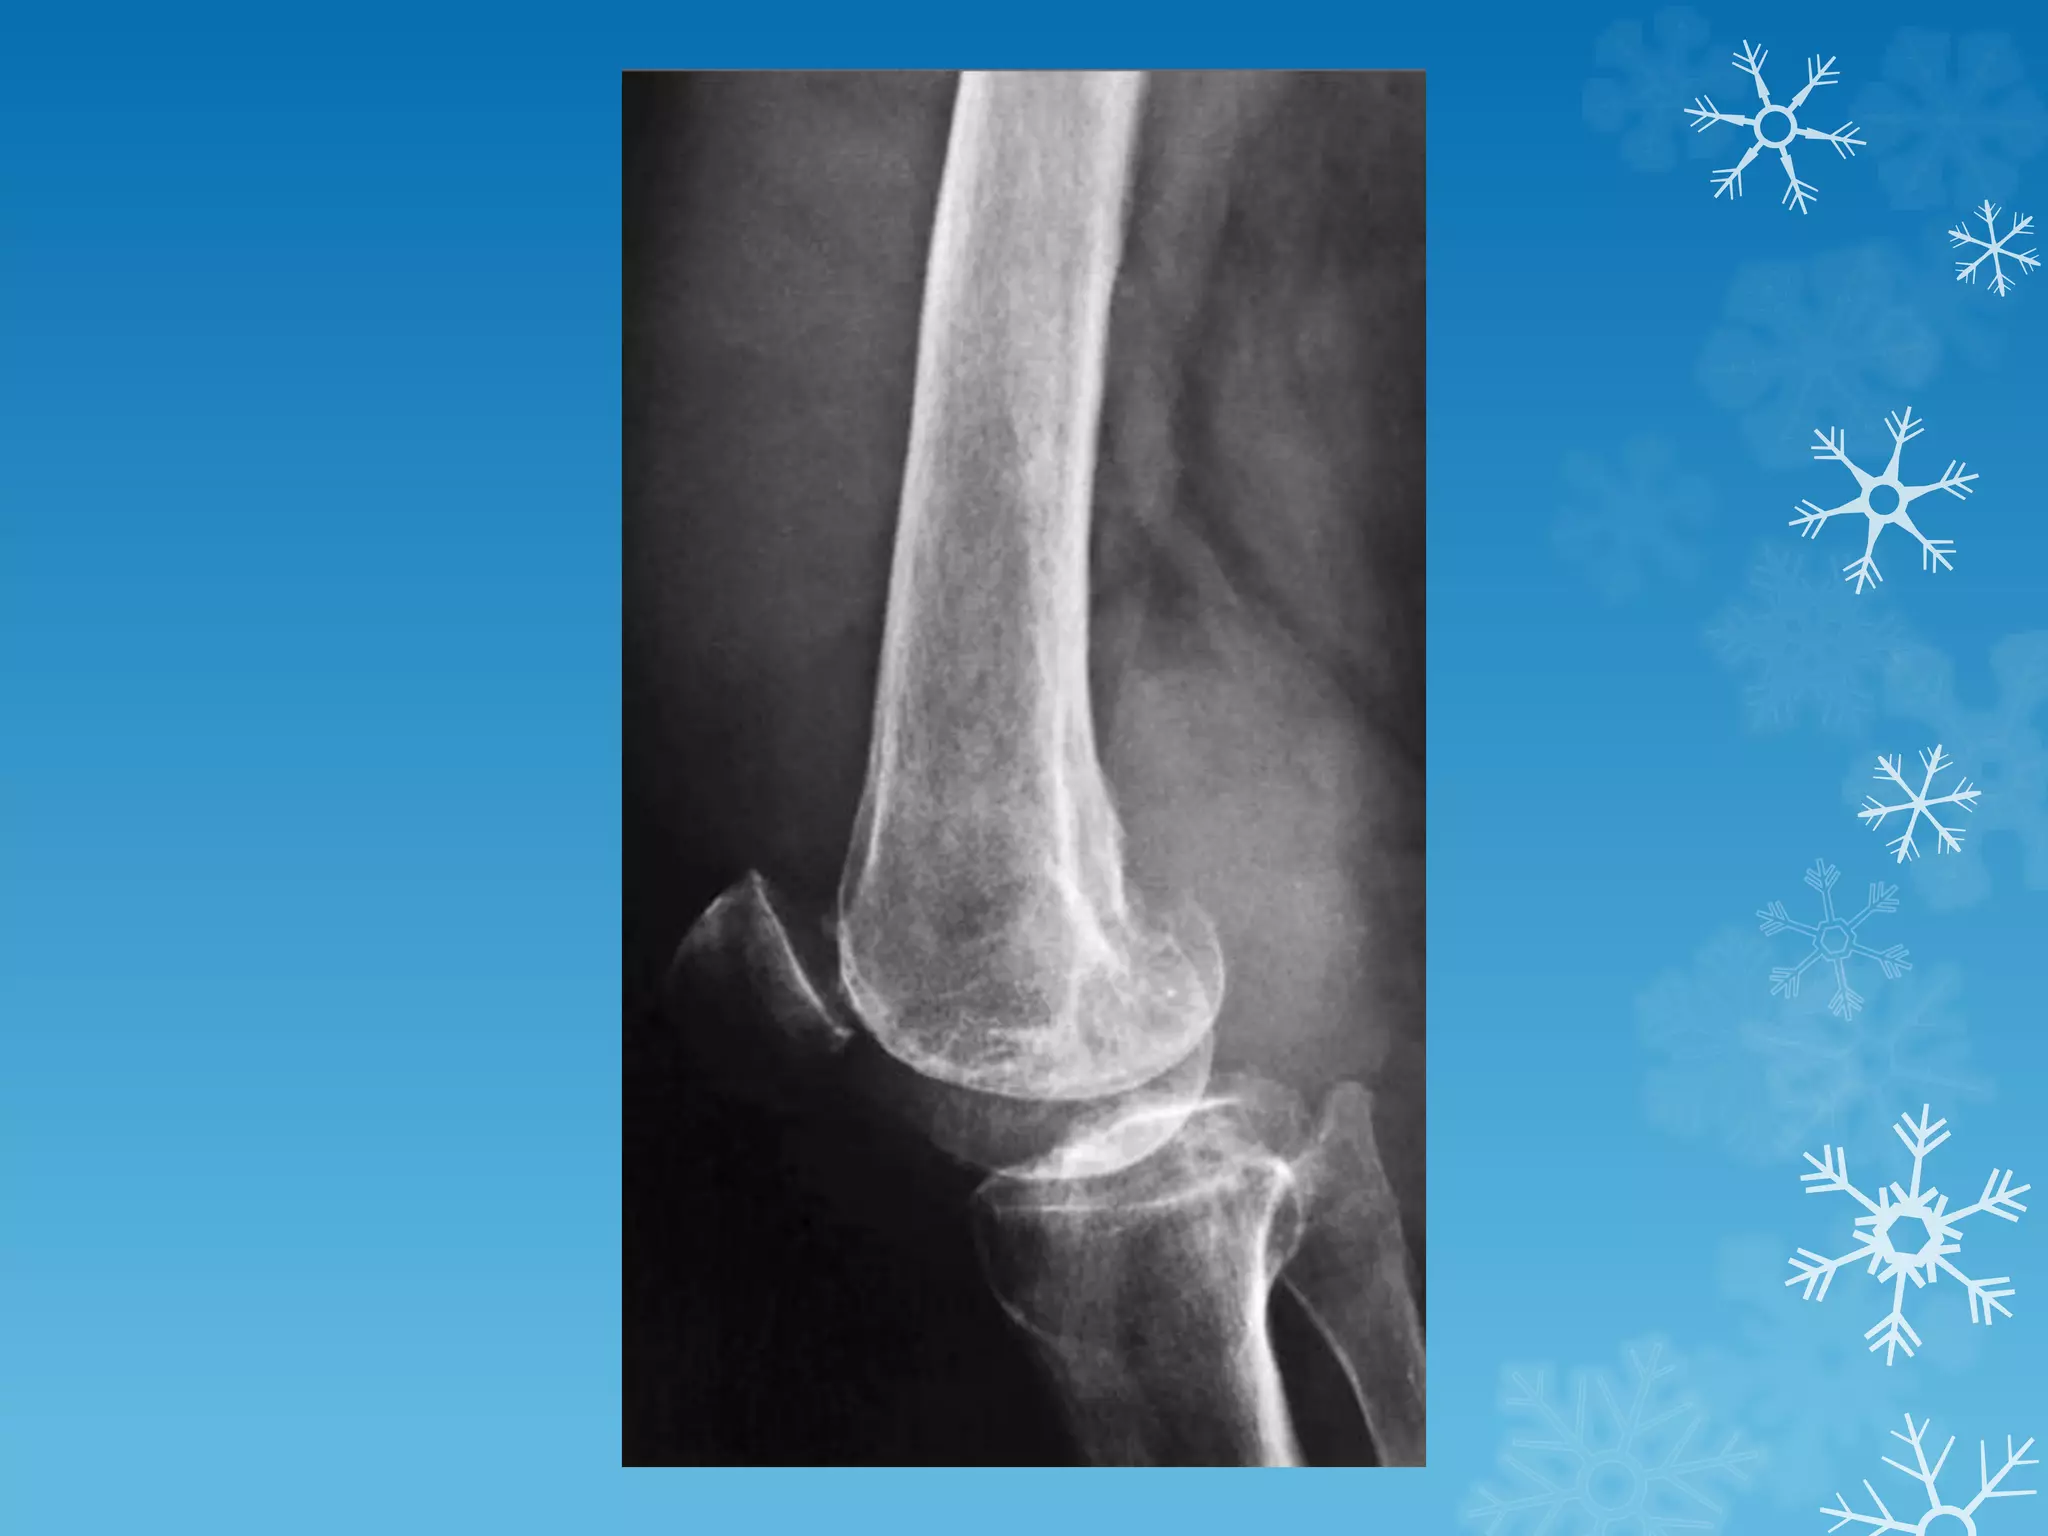

Shiny corner sign

The shiny corner sign, also known as a

Romanus lesion, is an early spinal finding in

ankylosing spondylitis.

These represent small erosions at the

superior and inferior endplates (corners on

lateral radiograph) of the vertebral bodies,

with surrounding reactive sclerosis.

Eventually the vertebral bodies become

squared